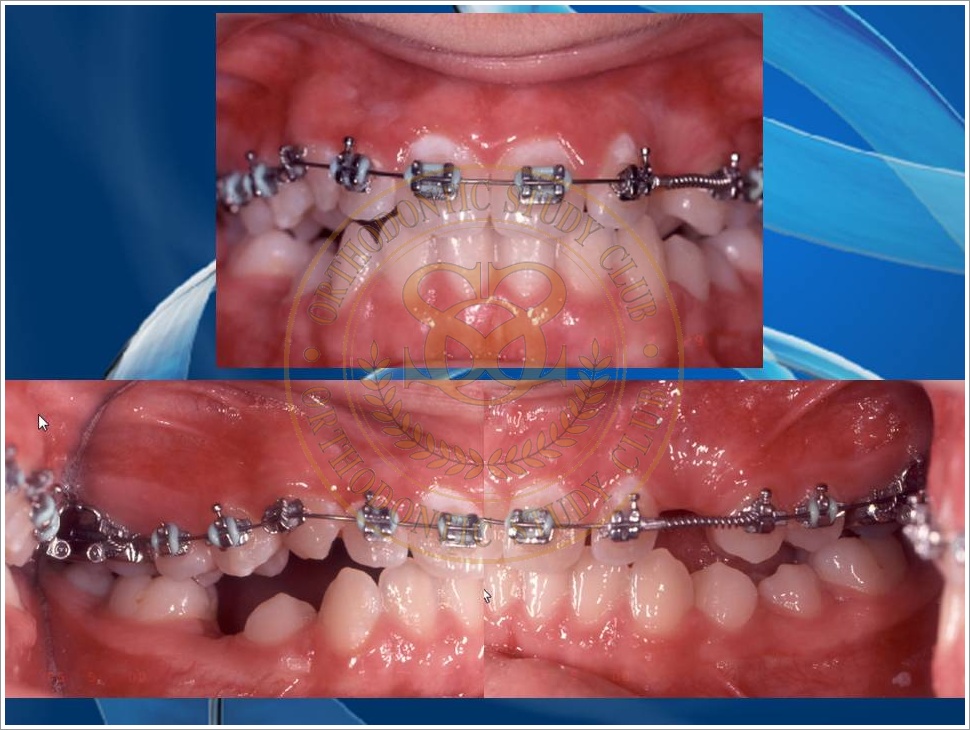

Treatment of Pseudo Class III (Class I Molar Relationship) and management of the embedded maxillary canine (Pt. Miss J.I.)